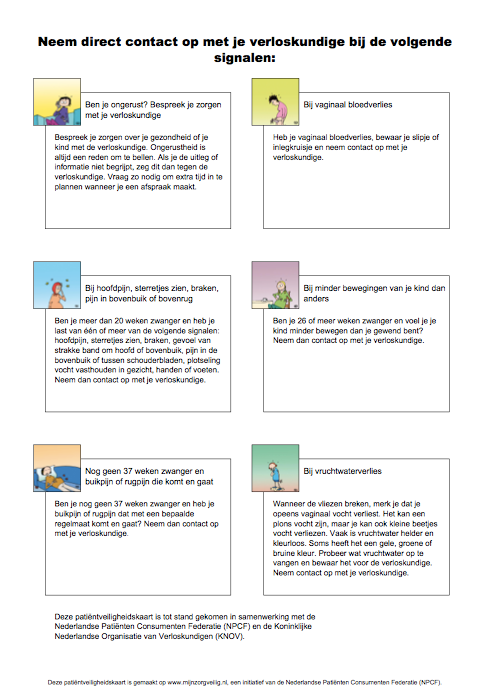

0-40 weken zwanger

Signalenkaart

Bij onderstaande klachten moet je contact met ons opnemen!!!!!!!!!!!!!!!!!!!